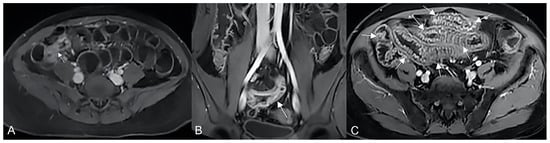

In the presence of small bowel thickening, degree, type, and extension of wall thickening must be indicated in the report. Depending on the wall thickness, thickening can be mild (<1 cm), moderate (>1 cm and <2 cm), or marked (>2 cm) [29] (Figure 16A).

Figure 16.

Degree of wall thickening and type of involvement along bowel circumference. (A) Axial T2-weighted image shows mild thickening (<1 cm) of an ileal loop in the pelvis (arrow). (B) Axial T2-weighted image shows moderate symmetric thickening (>1 cm and <2 cm) of a small bowel loop (black arrow), supported by edema of the submucosal layer. (C) Axial T2-weighted image shows marked asymmetric thickening (>2 cm) of an ileal loop in the pelvis (arrows); the other side of the bowel wall is less thick (arrowheads).

Thickening throughout the intestinal loop circumference might be eccentric (asymmetric) or circumferential (symmetric) depending on the type of involvement (Figure 16B,C) [29,30]. According to the length of the pathological bowel tract, thickening can be focal, segmental, or diffuse. Bowel thickening is defined as focal when the pathological tract is shorter than 5 cm in length (Figure 17A); segmental thickening refers to 6–40 cm in length of thickened small bowel (Figure 17B), while it is considered diffuse when a large amount of small bowel loops (>40 cm) is affected (Figure 17C) [29,30]. After contrast-medium injection, various patterns of wall enhancement can be described: stratified, white, and gray [30]. Contrast enhancement is classified as stratified when there is hyperintensity of the inner layer (muco-sa), hypointensity of the intermediate layer (submucosa), and hyperintensity of the outer layer (muscle and serosa layers); this is caused by mucosal hyperemia and submucosal edema. If stratified contrast enhancement is associated to fat deposits in the submucosal layer, it is called “fatty halo” sign [30,31].